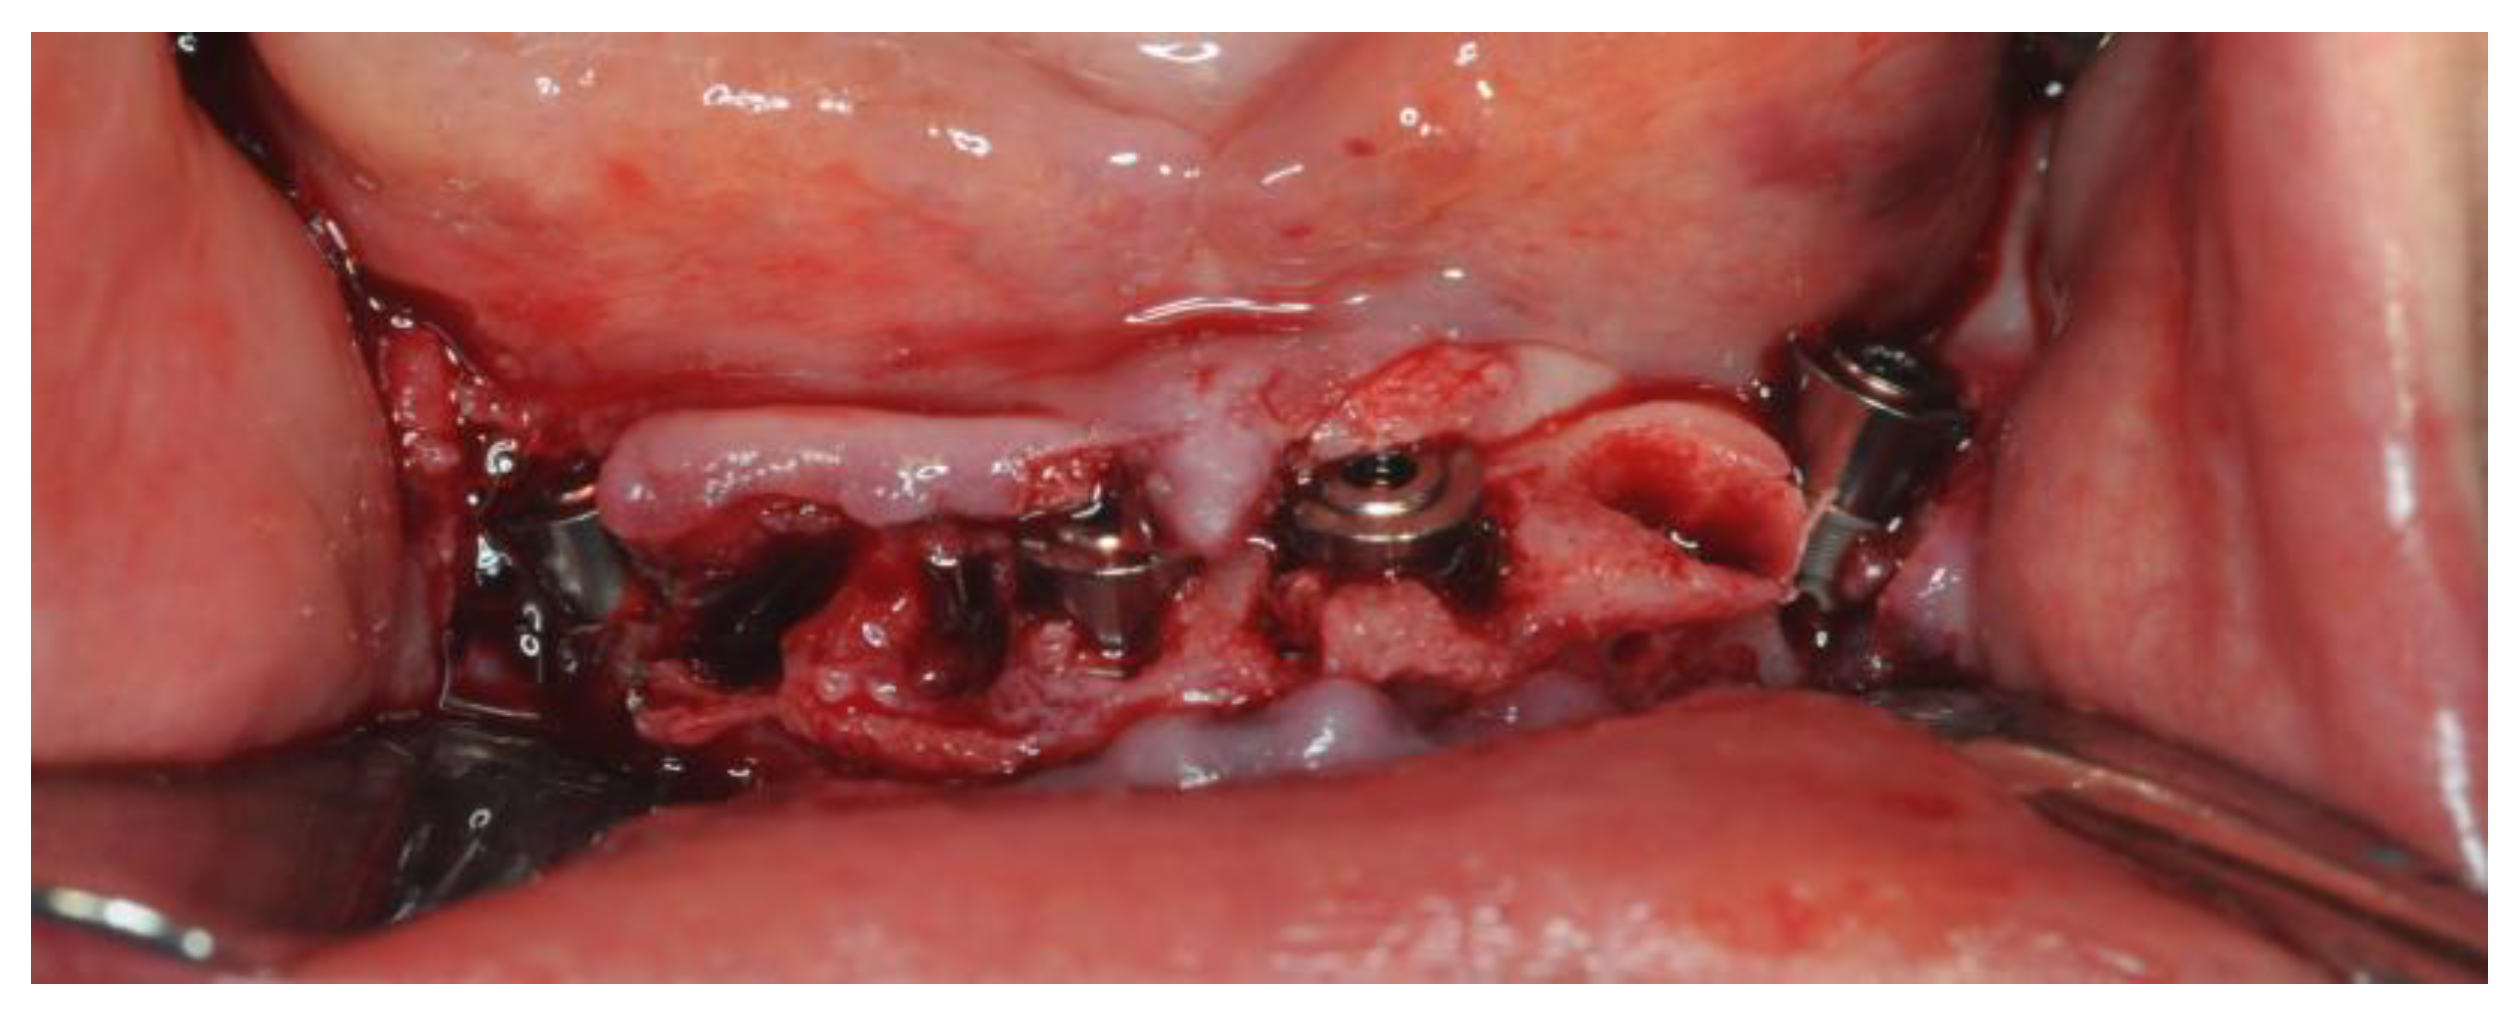

2.4. Surgery